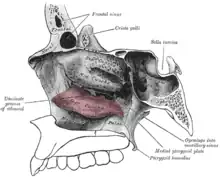

Le cornet nasal inférieur (ou cornet inférieur ou os turbinatum) est un os pair de la face situé à la partie inférieure des fosses nasales. Il forme le méat nasal inférieur.

Description

Le cornet nasal inférieur est une lamelle osseuse enroulée sur elle-même verticalement et allongée d'avant en arrière.

Il présente 2 faces, un bord supérieur et un bord inférieur.

Face médiale

La face médiale est convexe et fait face à la cloison des fosses nasales. Elle est marquée par de nombreux sillons correspondant aux vaisseaux sanguins.

Face latérale

La face latérale est concave. C'est la limite du méat nasal inférieur.

Bord supérieur

Le bord supérieur est mince et irrégulier.

Dans son quart antérieur, il s'articule avec la crête conchale du maxillaire.

La portion moyenne croise le hiatus maxillaire et présente trois processus :

- le processus lacrymal du cornet nasal inférieur (ou apophyse lacrymale ou apophyse nasale ou apophyse unguéale du cornet nasal inférieur) qui s'articule avec le bord inférieur de l'os lacrymal ; par ses bords antérieur et postérieur il contribue à former le canal lacrymo-nasal.

- le processus maxillaire du cornet nasal inférieur qui se recourbe en dehors et en bas du hiatus maxillaire qu'il obture en partie ; son bord postérieur s'articule avec le processus maxillaire de l'os palatin ;

- le processus ethmoïdal du cornet nasal inférieur qui s'articule avec le processus unciforme de l'os ethmoïde.

Dans son quart postérieur, il s'articule avec la crête conchale de l'os palatin.

Bord inférieur

Le bord inférieur est libre.